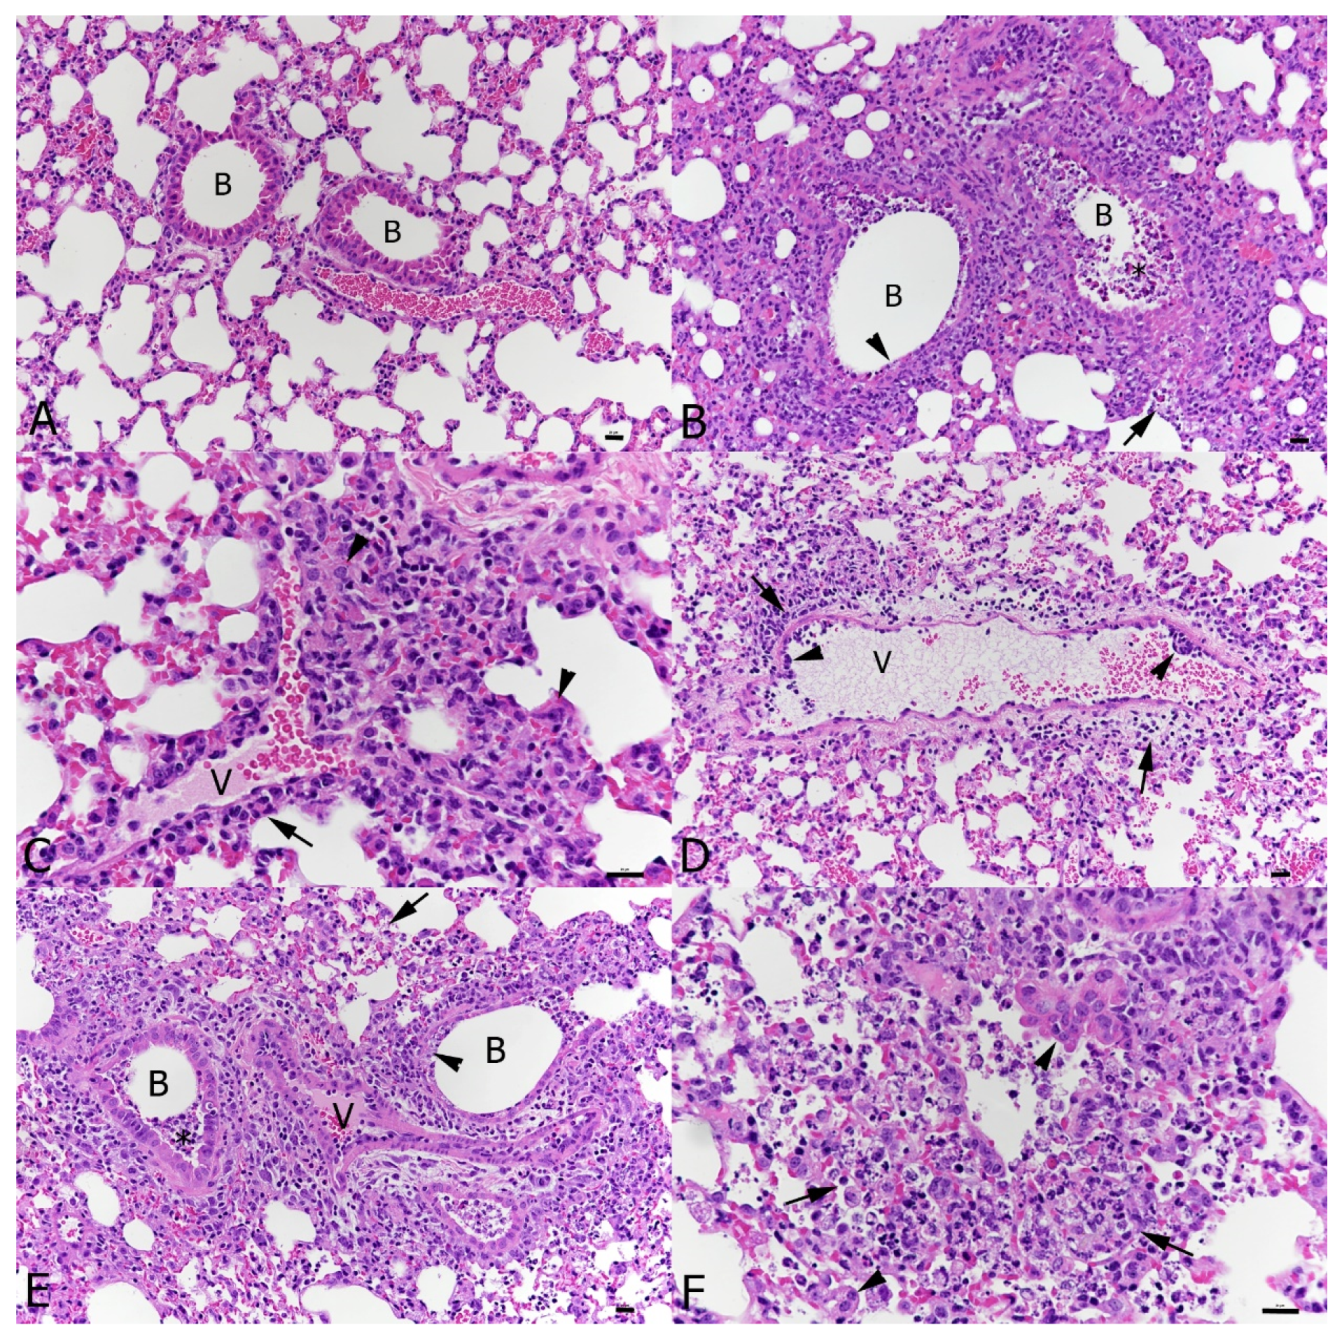

3.3. Coinfection Leads to Complementary and Enhanced Pathological Processes